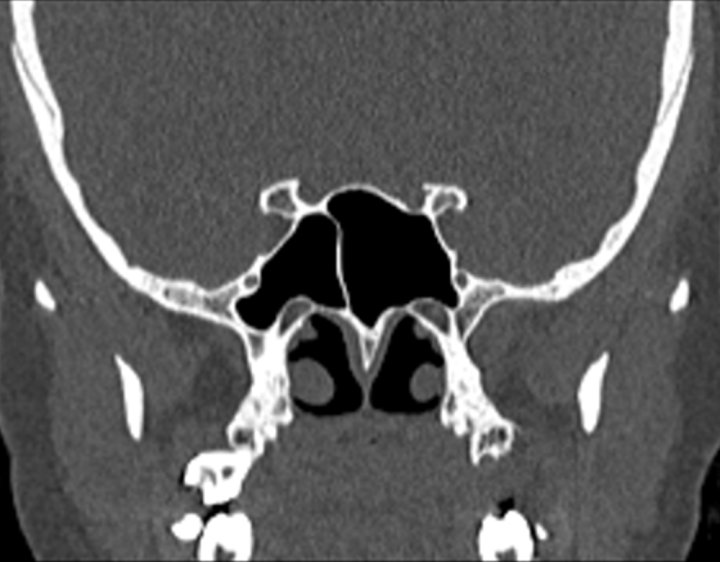

Click any image for labels.